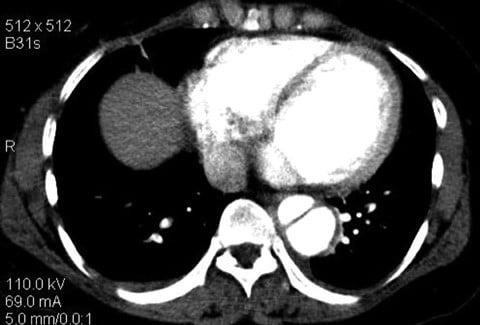

Aortic dissections can be classified using 2 systems: Stanford and DeBakey. The Stanford classification system categorizes dissections according to whether they require surgical repair (type A) or can be managed using medications to control blood pressure (type B).1 Type A dissections affect the ascending aorta, whereas type B dissections do not (see Figures 1 and 2).2 The DeBakey system also categorizes dissections by required medical intervention; however, this classification system details the process, or origination, of the dissection and is divided into types I, II, and III. Type I dissections originate in the ascending aorta, likely continue through the aortic arch, and often involve the descending aorta or even the entire aorta.2 Type II dissections affect only the ascending aorta, while type III dissections solely affect the descending aorta (see Box ).2 The most common aortic dissections occur in the descending aorta.3

Figure 2. CT scan showing an axial view of a Stanford type B aortic dissection. Reprinted with permission from Dr Avni K P Skandhan (Radiopaedia.org, rID: 25409) under the creative commons attribution-noncommercial-share alike 3.0 unported license.